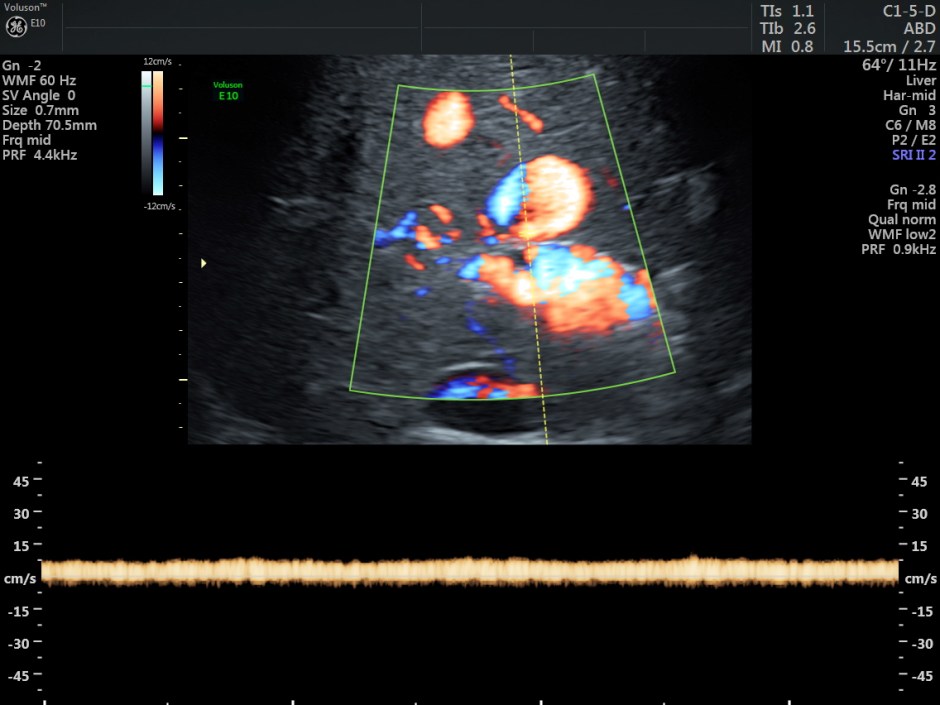

The venous flow is established by power doppler in the following pictures.

Reconstructed images show the feeding vessel and a vessel leaving the vascular structure.